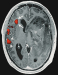

Functional Magnetic Resonance Imaging (fMRI) in Brain Tumour Patients European Association of NeuroOncology Magazine 2012; 2 (3): 123-128 PDF Summary Figures Keywords: brain mapping, brain neoplasms, functional, glioma, magnetic resonance imaging, motor cortex Functional magnetic resonance imaging (fMRI) is increasingly used in the work-up of brain tumour patients preoperatively to assess the relationship between the functionally eloquent cortex and brain pathology. In cases of presumed tumour localisation in or near eloquent brain areas, such as the motor cortex or language areas, fMRI may be advantageous to guide the neurosurgical approach, shorten surgery duration, and obtain prognostic information prior to surgery. For the assessment of the primary motor cortex a good correlation between fMRI and intraoperative electrocortical mapping (ECM) has been reported, with sensitivities and specificities ranging from 88–100 %. For the localisation of language representation areas validation results are controversial with sensitivities from 22–100 % and specificities from 0–100 %, rendering fMRI less suitable as the sole technique for language cortex localisation. For the assessment of hemispheric language lateralisation, however, > 90 % agreement between fMRI and the invasive Wada test has led to fMRI now mostly having replaced the Wada test for this indication. There are several limitations of fMRI including issues that are inherent to the technique such as spatial and geometric uncertainty, tumour effects on the fMRI signal, interand intra-individual variability, lack of discrimination between essential and modulating brain regions, and lack of information on the underlying white matter. Such shortcomings need to explicitly be taken into account in every patient. The careful use of fMRI is justified to aid neurosurgical planning but intraoperative ECM remains the gold standard for localising the eloquent brain cortex. |